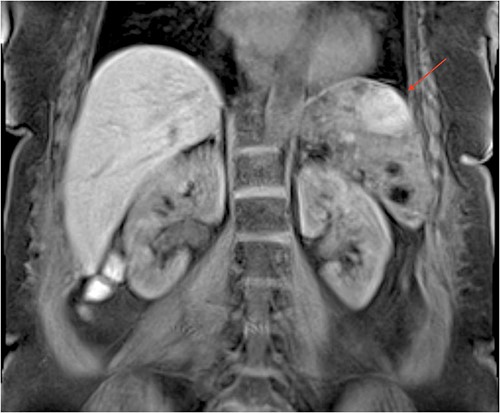

The patient was a 55-year-old female with relapsed large B cell lymphoma, severe thrombocytopenia with 17,000 platelets, and splenomegaly. Computed tomography (CT) (Fig. 1) and magnetic resonance (MR) (Fig. 2) images showed an enlarged spleen with multiple lesions, the largest measuring 3.5 cm, suspicious for lymphoma. Given the increased risk of intraoperative bleeding during splenectomy, a splenic artery embolization was performed the day before by using an Amplatzer plug (Fig. 3A and B), and platelets and fresh frozen plasma were prepared for the operation.

MR imaging of the abdomen (coronal section) revealing an enlarged spleen with multiple lesions, the largest one with heterogeneous enhancement.